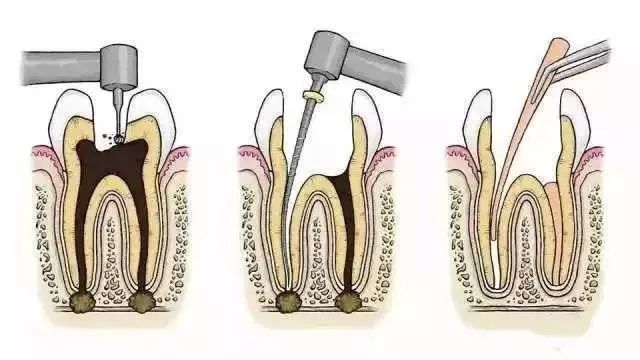

根管治疗的步骤?

Part

1

钻开腐败的牙质

Part

2

用根管在牙髓上做活塞运动

将坏的牙髓清理干净

Part

3

用银针锉去除牙髓

同时清洗移除牙髓残质及细菌